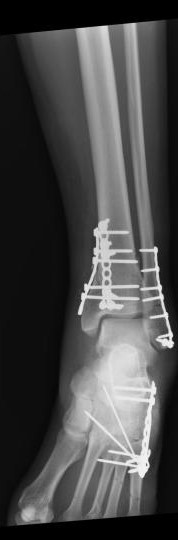

“Did you have bunion surgery?”

“Can you feel the screws in your ankle?”